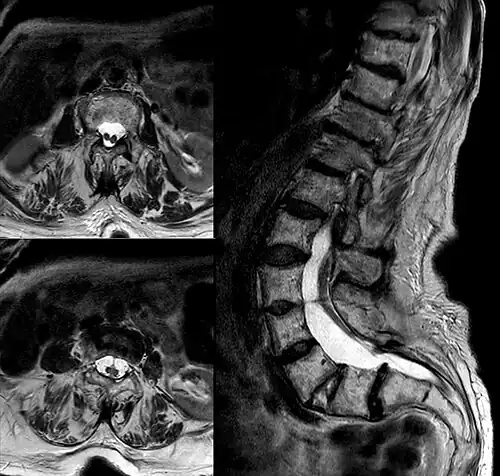

| Diastematomelia in MRI of lumbar spine. | |

In neurology, diastematomyelia (occasionally diastomyelia) is a congenital disorder in which a part of the spinal cord is split, usually at the level of the upper lumbar vertebra in the longitudinal (sagittal) direction. Females are affected much more commonly than males. This condition occurs in the presence of an osseous, cartilaginous or fibrous septum in the central portion of the spinal canal which then produces a complete or incomplete sagittal division of the spinal cord into two hemicords. When the split does not reunite distally to the spur, the condition is referred to as diplomyelia, which is true duplication of the spinal cord.[1]